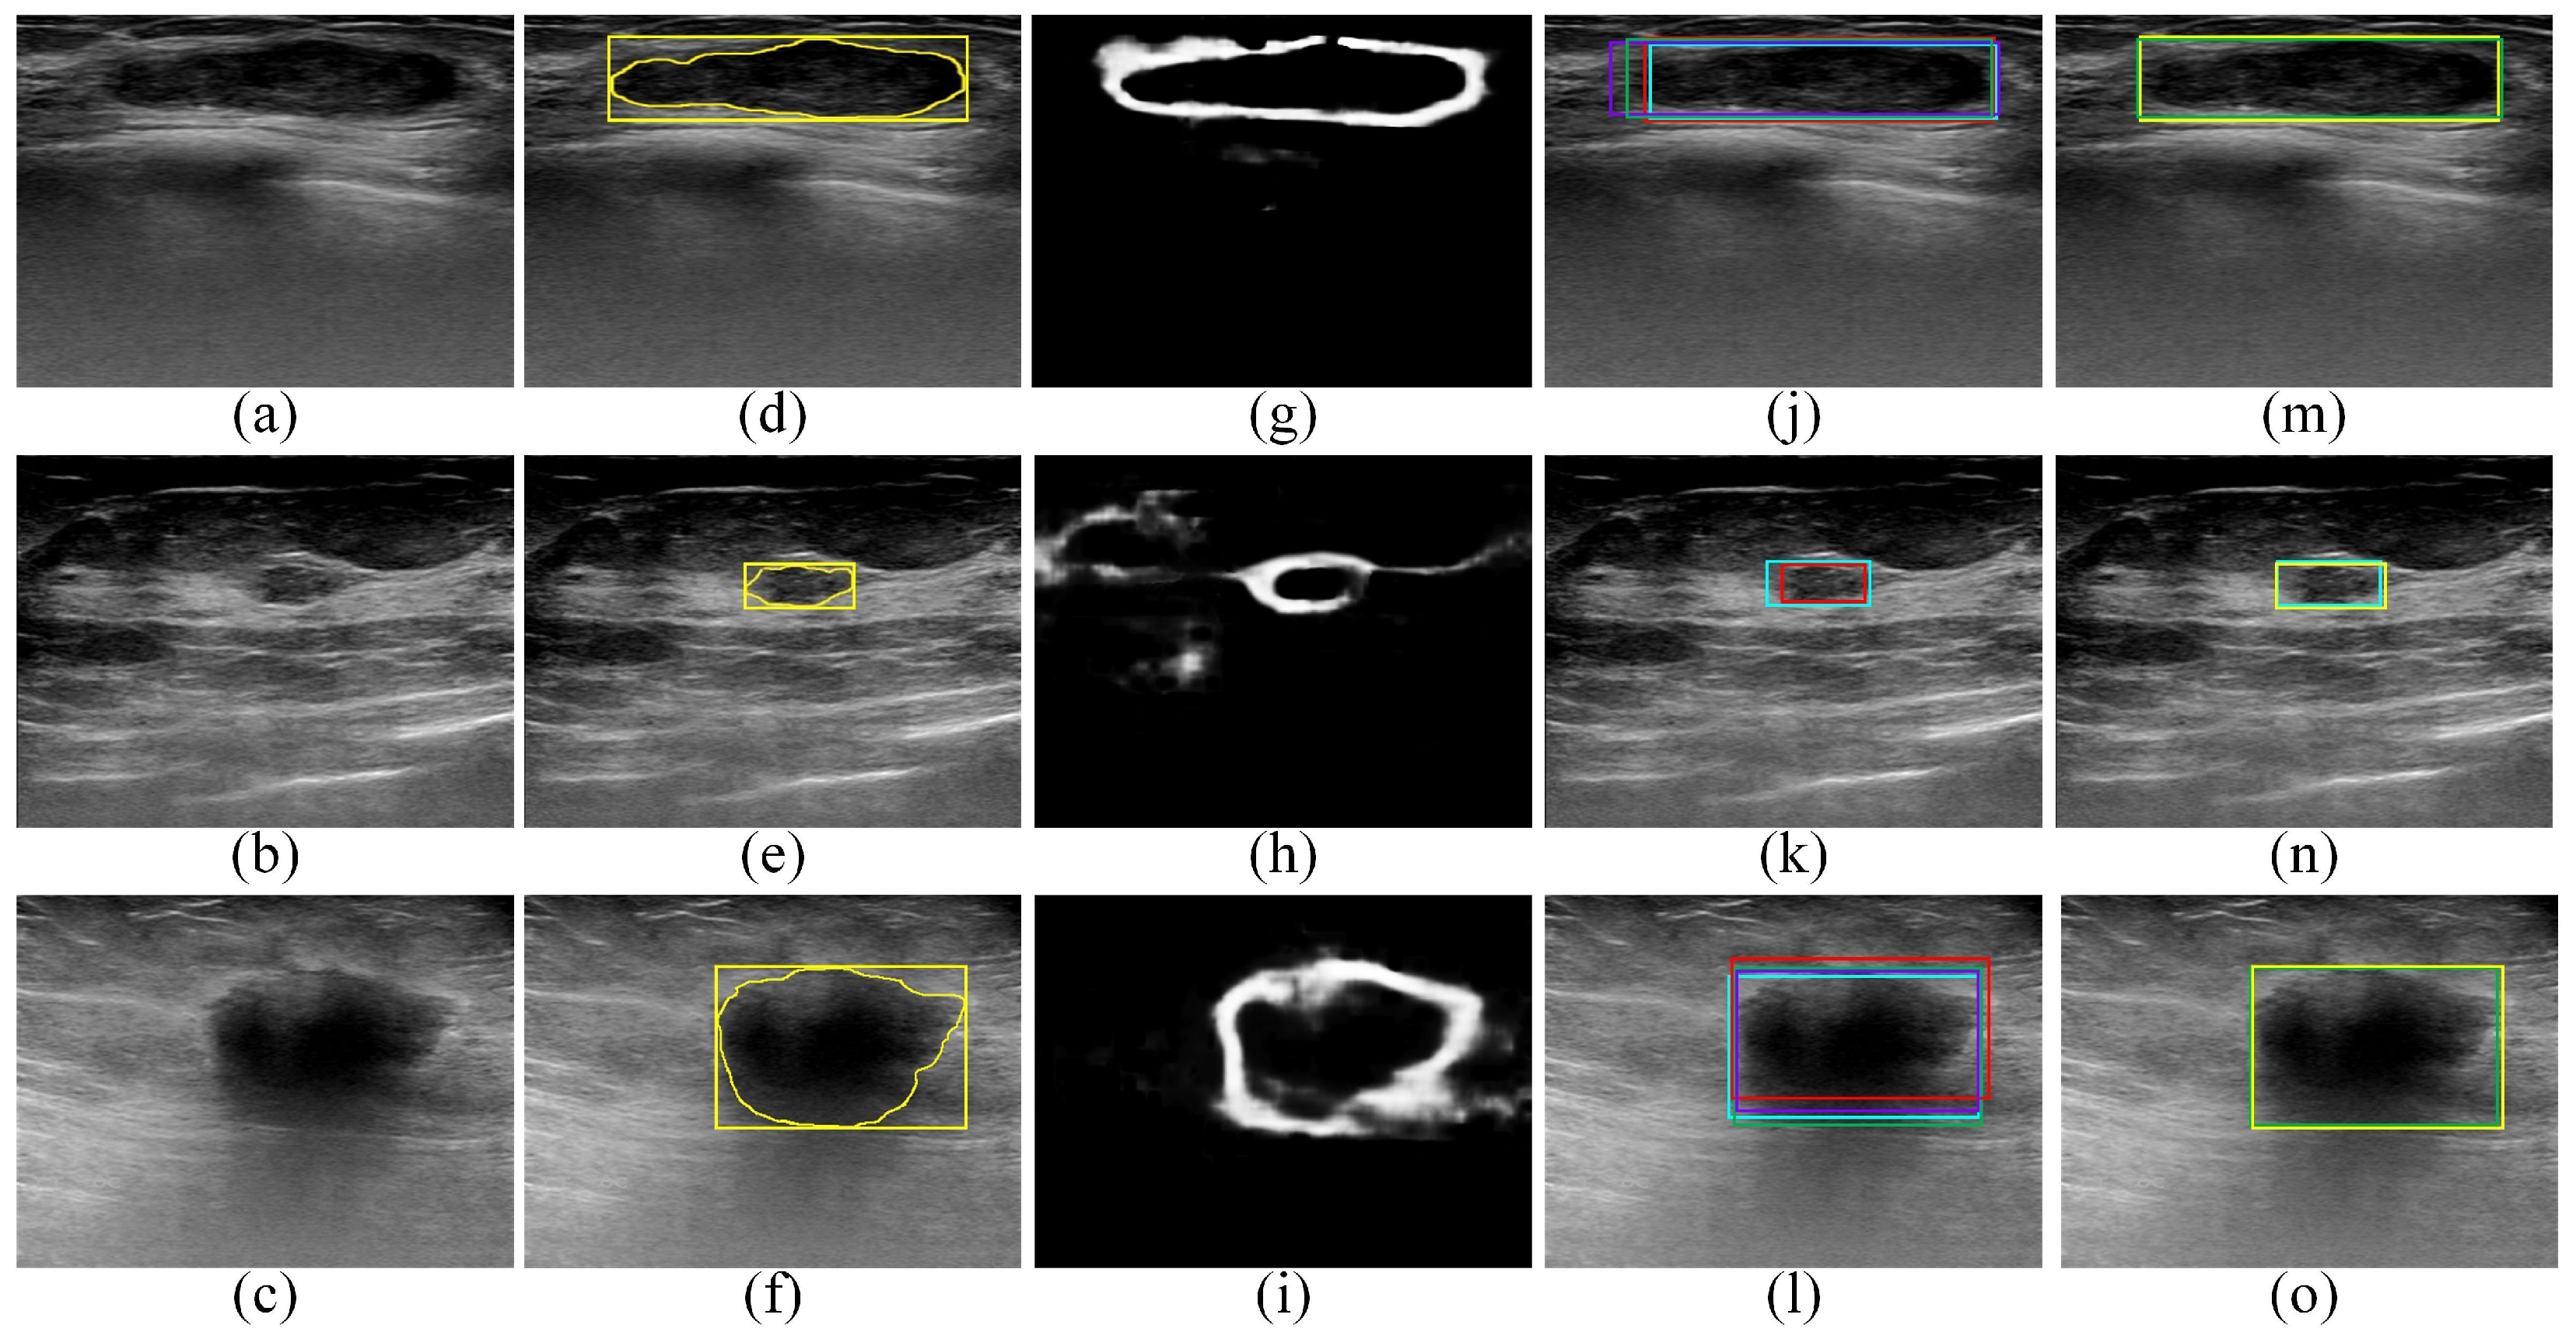

2.2.1. Transforming the BUS Images into Artificial RGB Images

2.2.2. Employing the Faster R-CNN Model to Localize ROIs That Contain the Tumors

2.2.3. Employing the SSD Model to Localize the ROIs That Contain the Tumors

2.2.4. Employing the EfficientDet-D0 Model to Localize ROIs That Contain Tumors

2.2.5. Employing the CenterNet Model to Localize ROIs That Contain Tumors

2.2.6. Employing the Proposed Edge-Based Selection Method to Select ROIs That Enable the Effective Detection of Regions That Contain Tumors